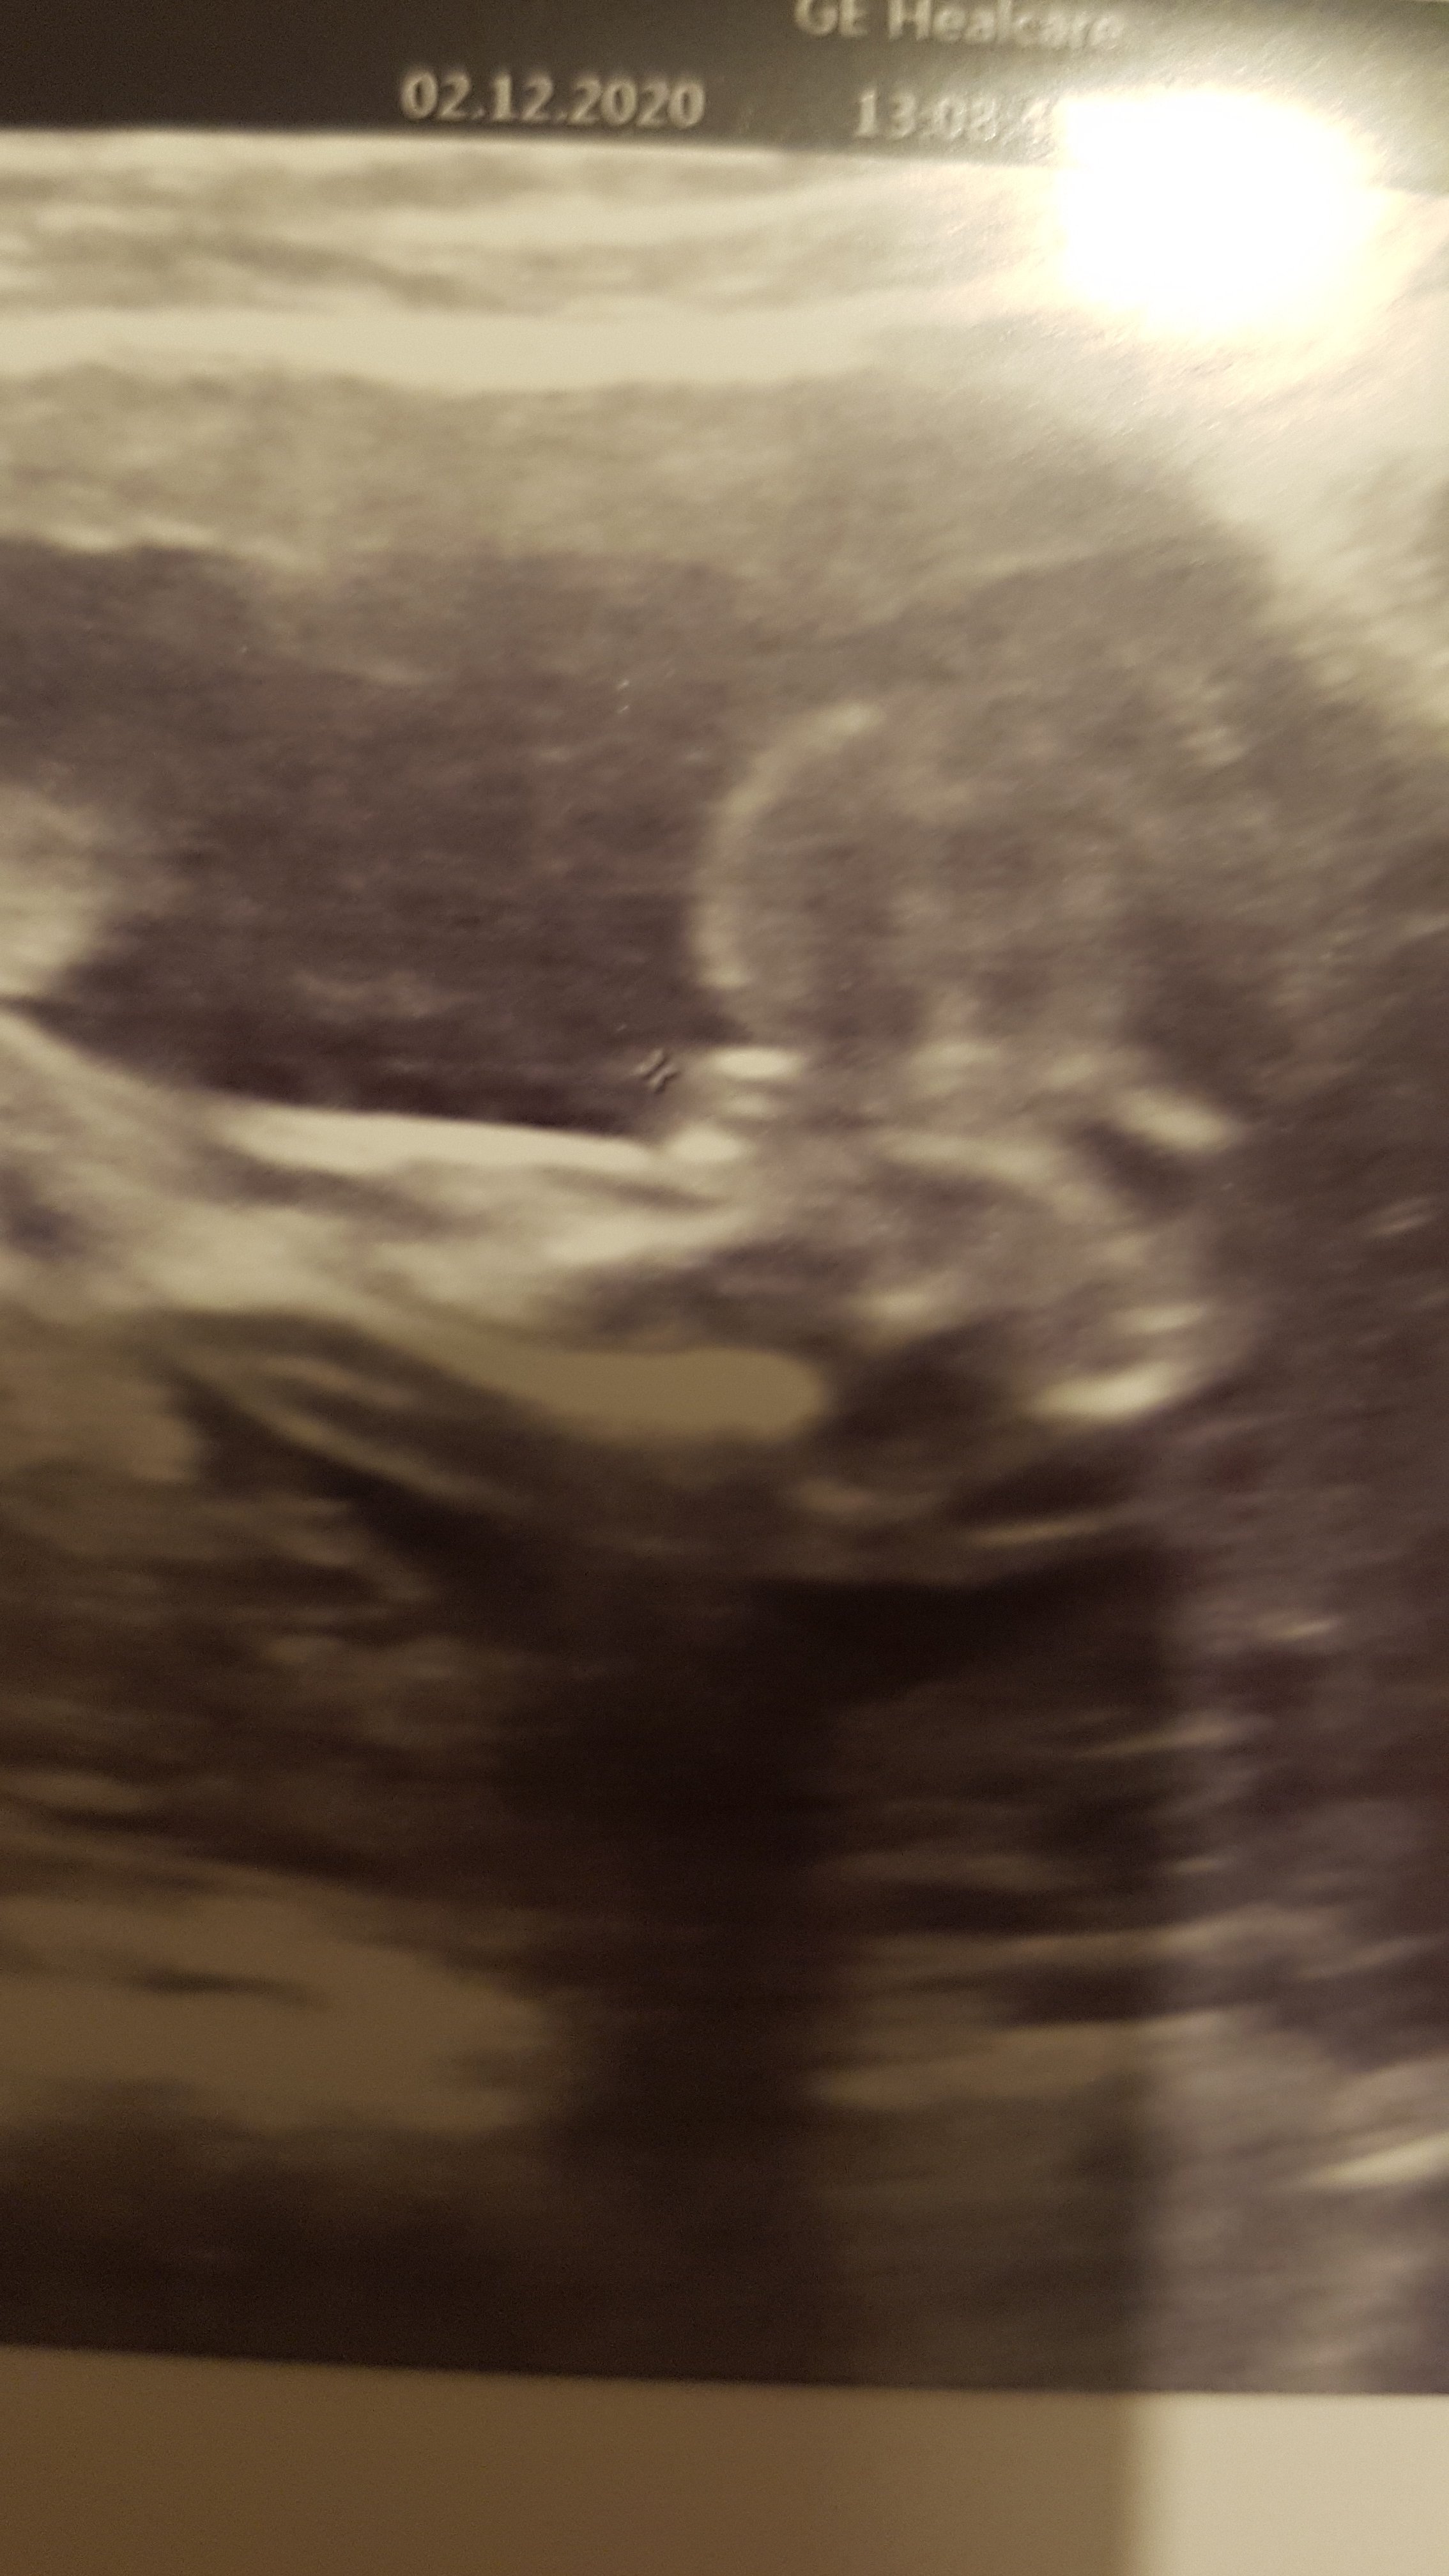

Jestem w 18 tygodniu. Lekarz.mowil 2tygodnie temu że chyba chłopiec A teraz że na 90%dziewczynka . Co sądzicie po fotce?

Załączniki

• 20201202_213713.jpg

20201202_213713.jpg

841,8 KB · Wyświetleń: 323

• 20201202_213717.jpg

20201202_213717.jpg

945,7 KB · Wyświetleń: 312